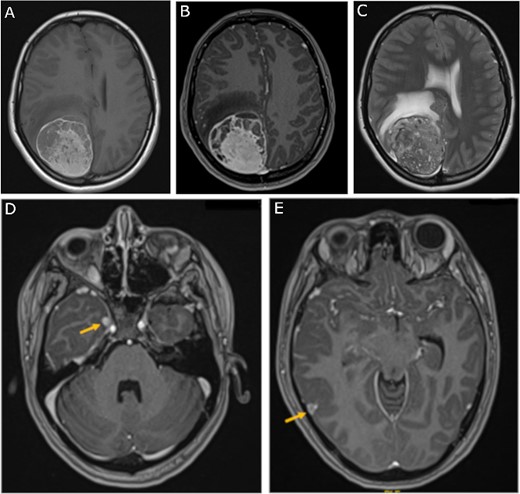

A 19-year-old woman presented with 2 months of intractable holocephalic headaches associated with nausea, occasional emesis, and generalized weakness which worsened over the 5 days preceding presentation. She had no past medical history and was not taking any regular prescribed medications. A computed tomography (CT) head (Fig. 1) revealed a right parietal mass measuring 6.2 × 5.5 × 5.8 cm. Her magnetic resonance imaging (MRI) re-demonstrated a large right parietal extra-axial mass as well as similar lesions in the right temporal lobe, with diffuse increased T1 signal without corresponding enhancement (Fig. 2).

Preoperative MRI; (A) pre-contrast, (B) post-contrast T1-weighted, and (C) T2-weighted axial MRI scans show a large right parietooccipital extra-axial mass with diffusely increased T1 signal without corresponding enhancement; (D, E) axial post-contrast T1-weighted MRI scans show two discrete lobular lesions along the medial aspect of the right temporal lobe and posterior cortical surface of the temporal lobe respectfully.